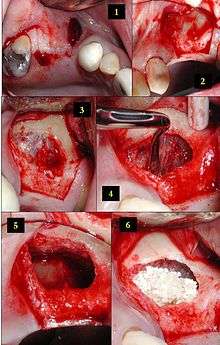

2) The soft tissue is flapped back to expose the underlying lateral wall of the left maxillary sinus.

3) The bone has been removed with a piezoelectric instrument, exposing the underlying Schneiderian membrane, which is the lining of the maxillary sinus cavity.

4) Through careful instrumentation, the membrane is carefully peeled from the inner aspect of the sinus cavity.

5) The membrane has been reflected from the internal aspect of the inferior portion of the sinus cavity; one can now visualize the bony floor of the sinus cavity without its lining membrane (note the triangular ridge of bone within the sinus, known as an Underwood's septum).

6) The newly formed space within the bony cavity of the sinus yet inferior to the intact membrane is grafted with human cadaver allograft bone. The floor of the sinus will now be roughly 10mm or so more superior than it was before, providing enough room to place dental implants into the edentulous site.